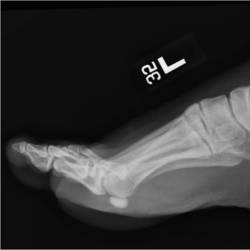

Gallery of Unlabled Radiographs from Lecture (Dr. French) - 2020

Click a thumbnail to enter the gallery display. Click the file name link at the bottom left of the gallery display to view the image at high resolution.

Labeled Plates from Lecture (Dr. French) - 2020

RadiologyLowerLimbThoraxQuestionPoolLabeled_01_2020.pdf

Click right side of plate to step forward or left side of plate to step backward.